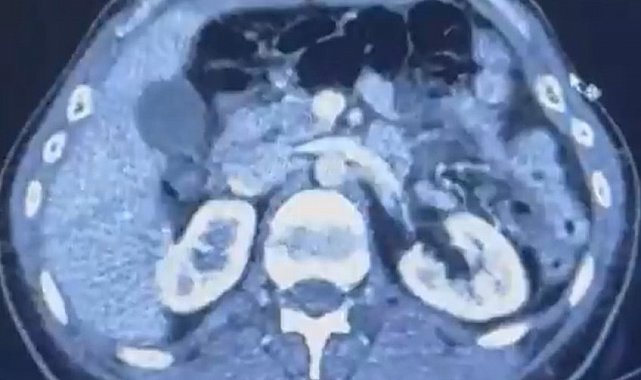

Edinilen bilgiye göre Narkotik Suçlarla Mücadele Şube Müdürlüğü ekiplerince uluslararası uyuşturucu madde ticareti yapan kurye şahıslara yönelik gerçekleştirilen çalışmalarda, İran'dan Türkiye'ye uyuşturucu madde getirdiği tespit edilen şüpheli şahısların yakalanması amacıyla operasyon düzenlendi. Düzenlenen operasyonda; S.C., R.B.C. ve G.M. yakalandı. S.C. ve R.B.C.'nin Kayseri Şehir Hastanesi'nde yapılan iç beden muayenelerinde, mide kısımlarında bulunduğu tespit edilen 50 adet kapsül şeklinde toplam 554 gram uyuşturucu madde ele geçirildi. Şüpheliler gözaltına alınarak haklarında 'Uyuşturucu Madde Ticareti Yapmak' işlem başlatıldı.